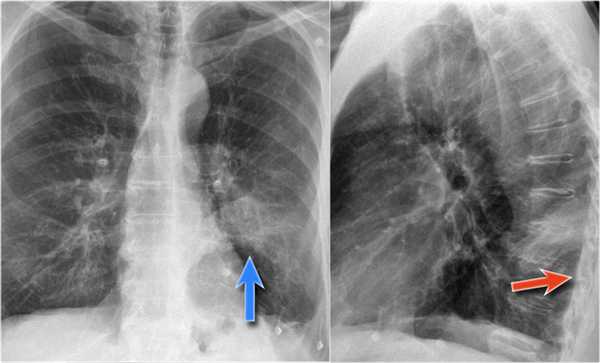

Также очень частым проявлением ателектаза является подъем диафрагмы, что хорошо визуализируется на ниже представленной рентгенограмме (указано синий стрелкой).

У данного пациента карцинома легкого с билатеральным метастазированием в легкие (указано красными стрелкам).